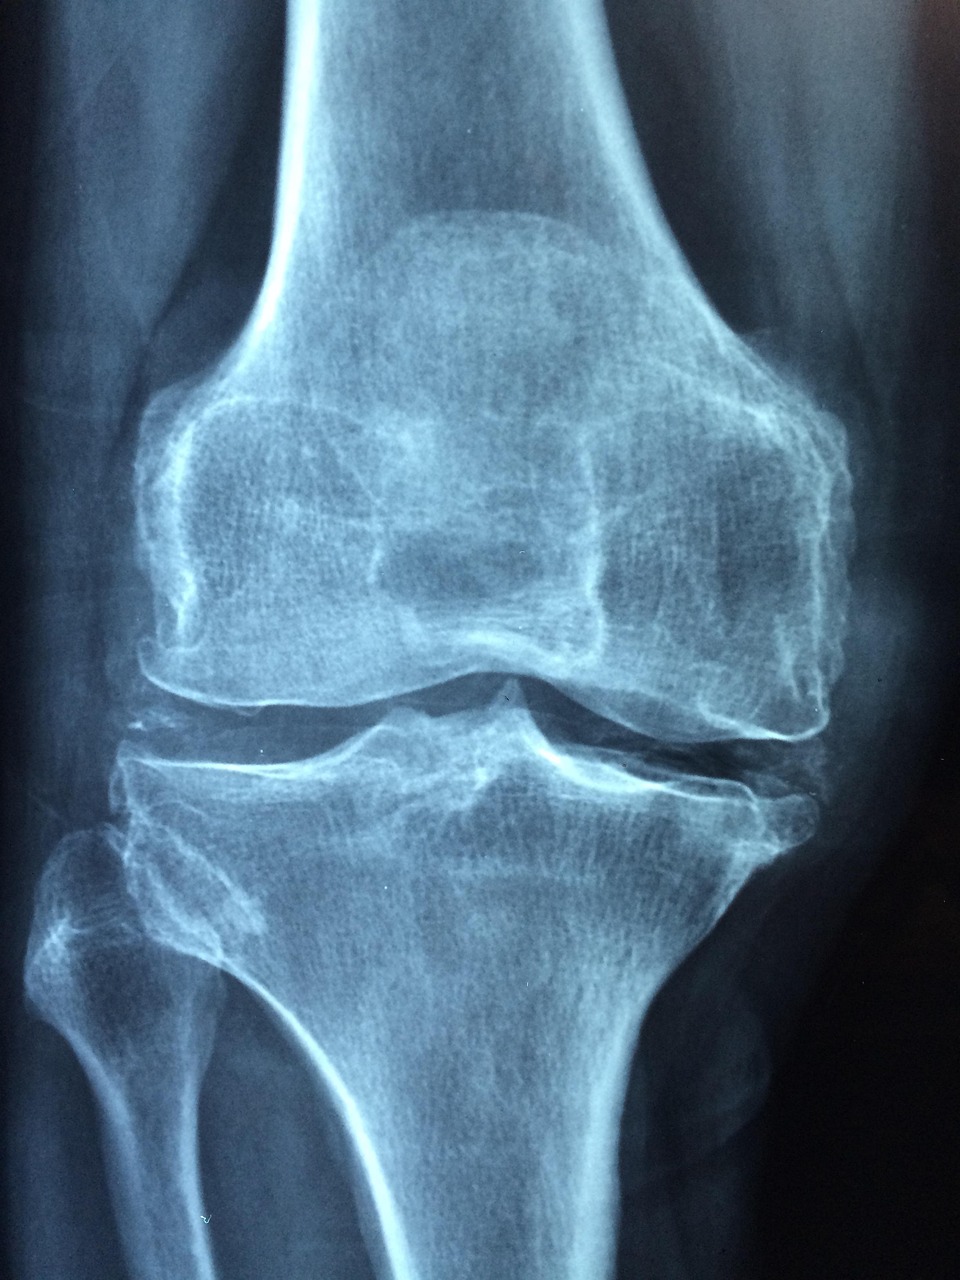

Your interferential therapy session begins with a thorough evaluation using our precision X-ray diagnostics to identify specific treatment areas. During treatment, you'll feel a gentle tingling sensation as the therapeutic currents work to reduce pain and promote healing. Sessions typically last 10-15 minutes and are completely comfortable, so much so that some of our patients fall asleep during treatment.